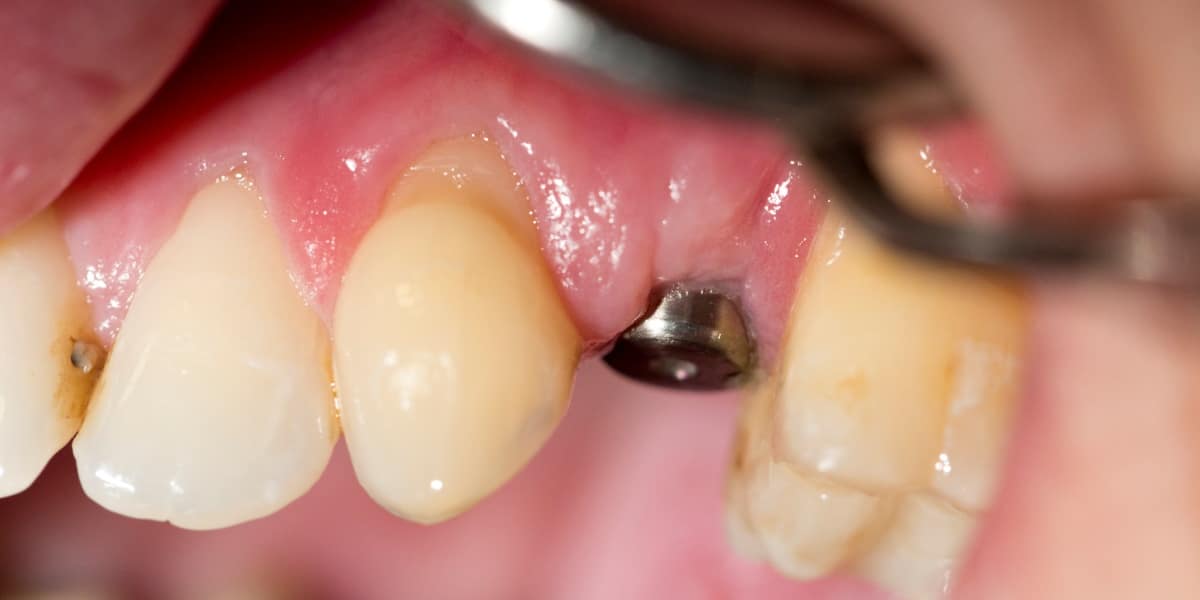

Zubní implantát je alternativním protetickým řešením, neboť chybějící zuby lze kromě klasického můstku klinicky vhodněji nahradit zubním implantátem, který splňuje všechny funkce původního zubu a navíc je jeho přirozenou a věrnou kopií, bez nutnosti zbrousit (degradovat) jiné okolní zuby (jako v případě můstku).